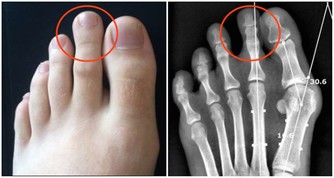

3、關節疼痛

類似於關節炎的症狀(如關節痛、噁心、嘔吐、疲勞和食慾減退)都是與肝病相關的症狀,特別是自身免疫性肝炎。

這種病是免疫系統錯誤地向細胞和肝臟組織發起了攻擊,它更常見於女性。